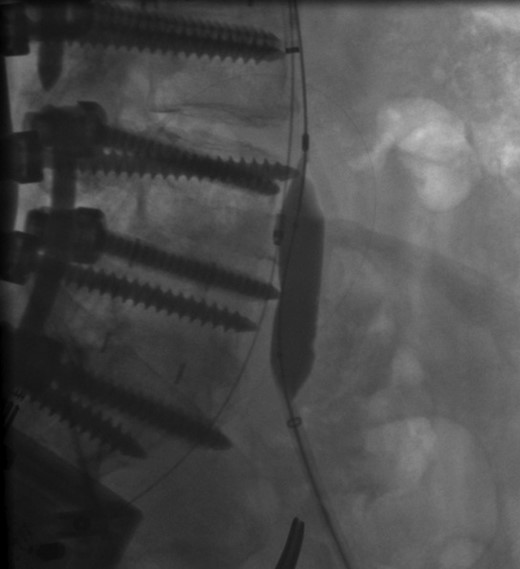

The patient was scheduled for left iliac vein stent placement. During the procedure, impingement was noted upon the posterior aspect of the vein. At this location, there was perforation of a pedicle screw through the anterior cortex of her L5 vertebral body, from prior spinal fusion. This interaction was well visualized during intraluminal inflation of a 12 mm × 40 mm high-pressure balloon (Fig. 2) and was also seen after final stent placement (Fig. 3). Because the screw tip was completely unyielding, a 14 mm × 60 mm Wallstent was used instead of the 16 mm stent we typically use, so as to avoid undue compression of her overlapping right common iliac artery. After the procedure, the patient's symptoms were greatly improved. Follow-up venography performed 4 months postoperatively showed a patent stent with slight eccentric compression at the protruding screw and no evidence of in-stent stenosis.

Perforation of a pedicle screw through the anterior cortex of L5 vertebral body visualized during intraluminal inflation of a 12 mm × 40 mm high-pressure balloon.

Intraoperative radiograph showing posterior compression of a wall stent within the left common iliac vein.